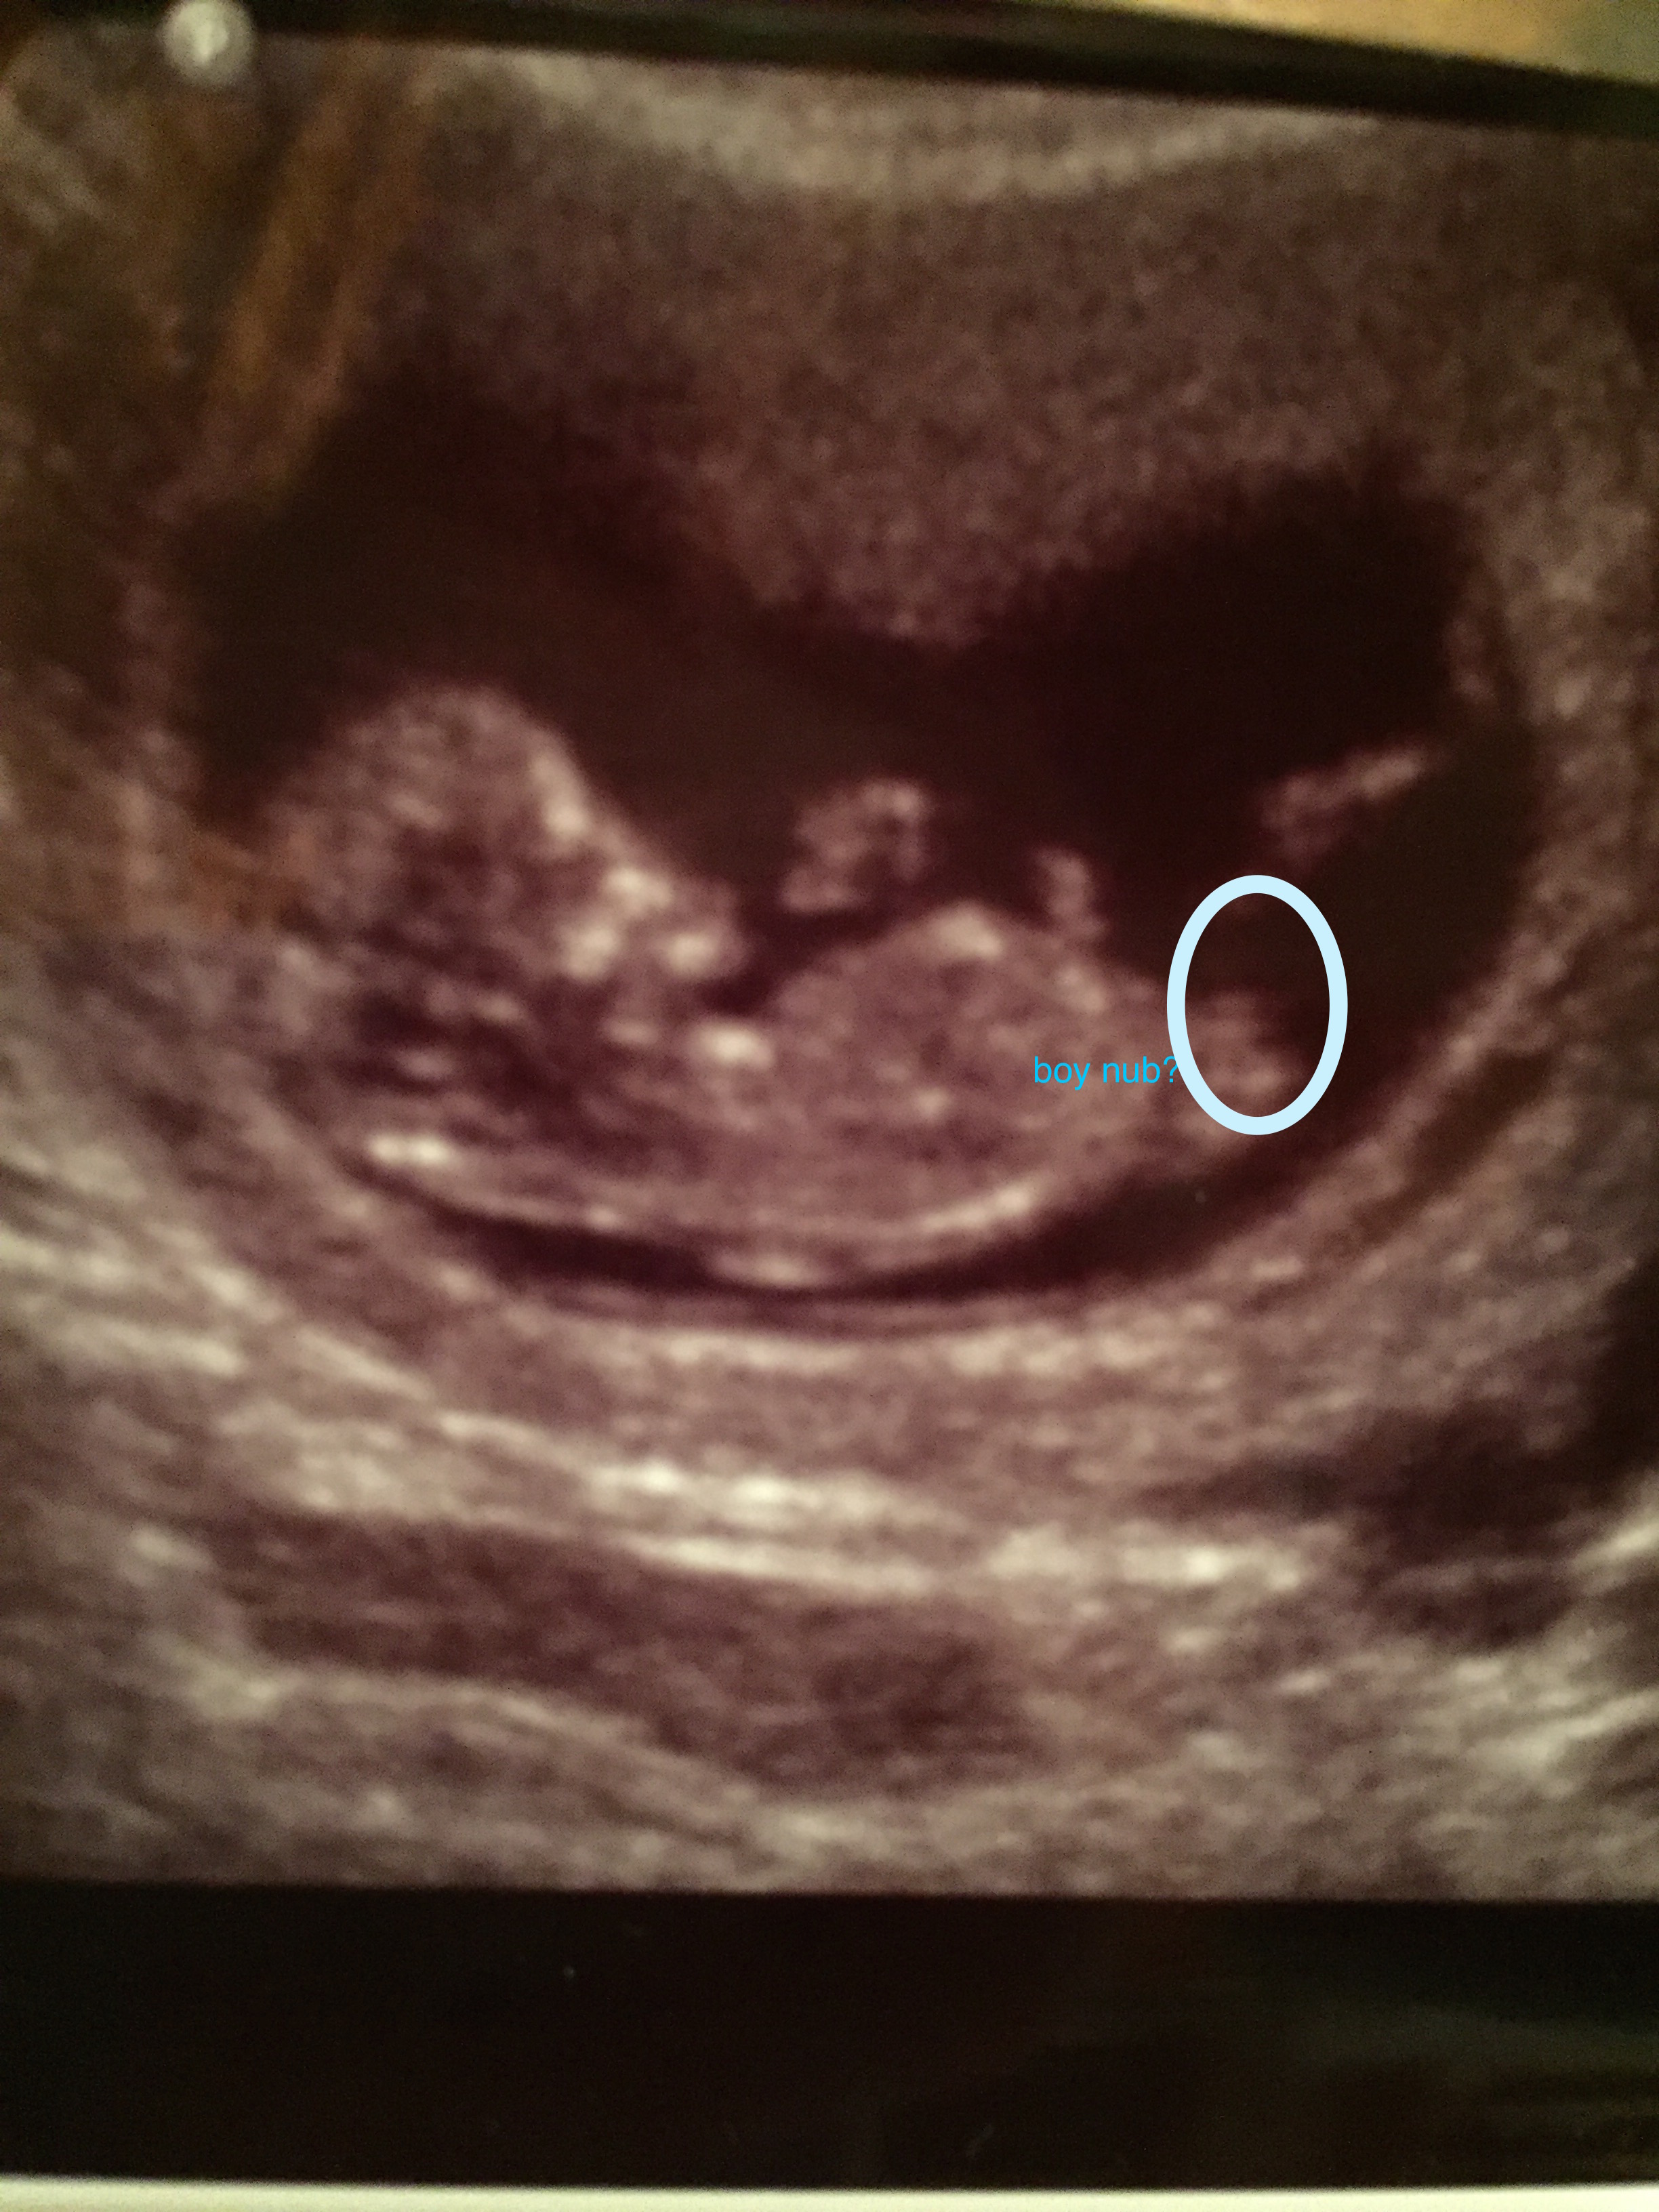

Attachment 28376Someone told me this is a boy nub. I previously posted two pics on here and got all boy guesses from other photos but someone said by looking at this picture from my sonogram( I didn't post this picture since I didn't feel like I could see anything) that the circle area is a boy nub. Any insight would be appreciated.Gender scan is on friday so any last guesses? Thanks so much ladies!!!Attachment 28374